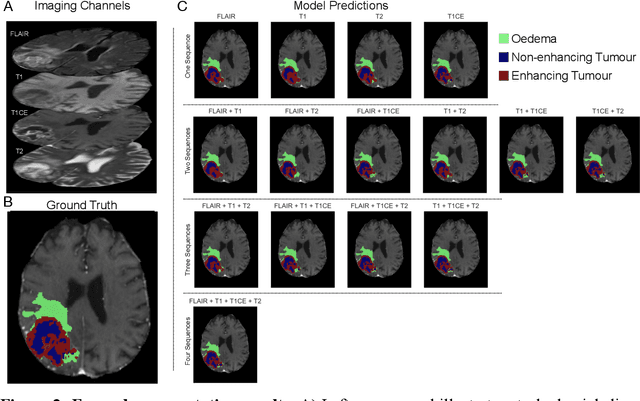

Abstract:Background: The complex heterogeneity of brain tumours is increasingly recognized to demand data of magnitudes and richness only fully-inclusive, large-scale collections drawn from routine clinical care could plausibly offer. This is a task contemporary machine learning could facilitate, especially in neuroimaging, but its ability to deal with incomplete data common in real world clinical practice remains unknown. Here we apply state-of-the-art methods to large scale, multi-site MRI data to quantify the comparative fidelity of automated tumour segmentation models replicating the various levels of completeness observed in clinical reality. Methods: We compare deep learning (nnU-Net-derived) tumour segmentation models with all possible combinations of T1, contrast-enhanced T1, T2, and FLAIR imaging sequences, trained and validated with five-fold cross-validation on the 2021 BraTS-RSNA glioma population of 1251 patients, and tested on a diverse, real-world 50 patient sample. Results: Models trained on incomplete data segmented lesions well, often equivalently to those trained on complete data, exhibiting Dice coefficients of 0.907 (single sequence) to 0.945 (full datasets) for whole tumours, and 0.701 (single sequence) to 0.891 (full datasets) for component tissue types. Incomplete data segmentation models could accurately detect enhancing tumour in the absence of contrast imaging, quantifying its volume with an R2 between 0.95-0.97. Conclusions: Deep learning segmentation models characterize tumours well when missing data and can even detect enhancing tissue without the use of contrast. This suggests translation to clinical practice, where incomplete data is common, may be easier than hitherto believed, and may be of value in reducing dependence on contrast use.